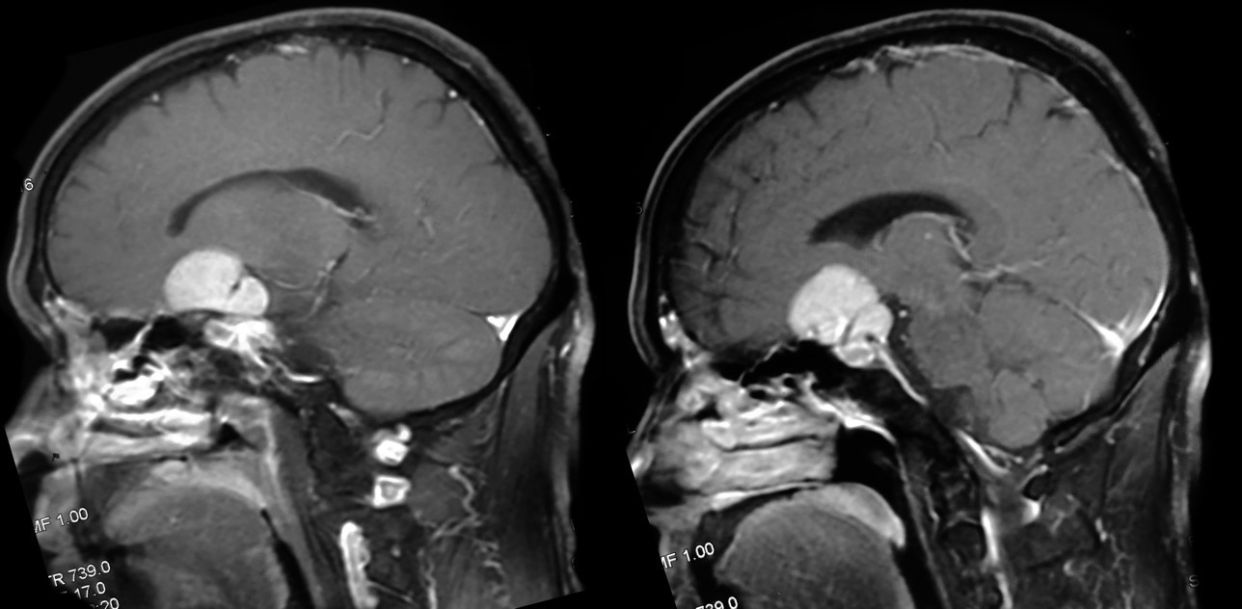

病例2:男性,55岁,因左眼视力进行性下降1年余入院。

查体:神清,对答可,粗测左眼视力全盲,右眼 0.8 ,左瞳2.5mm,直接对光反射消失,间接对光反射存在,右瞳直接对光反射存在,间接对光反射消失,眼球各方向活动正常,四肢肌力正常,深浅感觉正常,病理征(-)。

MRI检查: